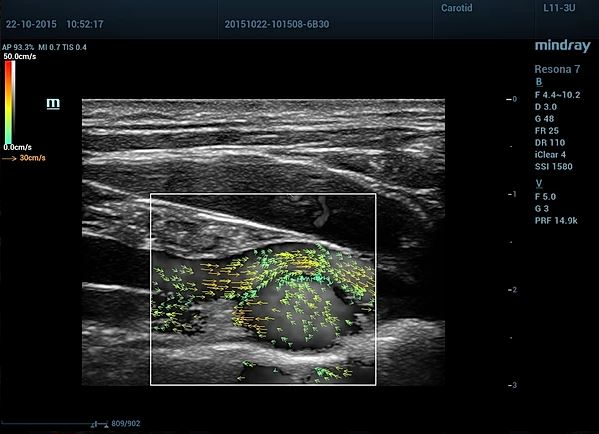

Изюминкой Reasona считается технология зонного сканирования и векторная отрисовка кровотока и оценка его скорости (V-Flow).